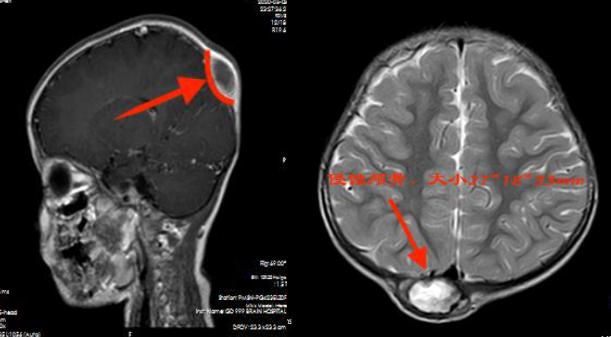

▲术前影像检查

我院神经外三科副主任杨宝应在查看薇薇的影像资料时,发现薇薇的右侧顶骨有一椭圆形骨质破坏,大小约为3X3cm²;缺损区边缘锐利清晰,与正常颅骨界线分明;已有软组织形成。杨宝应初步诊断是LCH。